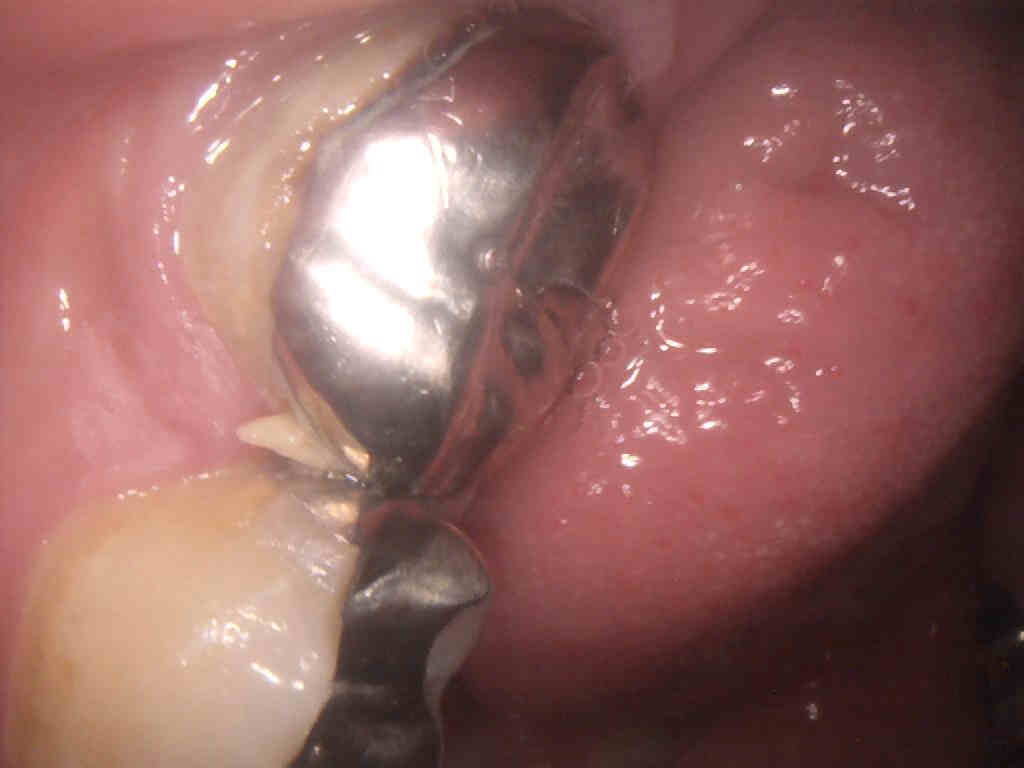

③セラミック製の歯が破損した

セラミックは非常に硬質な素材ですが、強い衝撃への耐性は低くなっています。これはセラミック製の食器をイメージしていただくとご理解いただけるでしょう。天然歯の硬度が400MPa、セラミックも約400MPaでほぼ同等の硬度となります。そのため、日常的に歯の食いしばりや、就寝時の歯ぎしりの習慣があると、天然歯が摩耗・削れるのと同様にセラミックも破損するトラブルが発生する可能性があります。セラミック歯は修復が困難な人工歯のため、十分な注意が必要です。ボトックス(ボツリヌストキシン)注入治療で筋力を抑制するか、就寝時のマウスピース装着、破損防止のケアを行いましょう。

④被せ物を装着した歯に虫歯が発生した

セラミック治療(セラミック矯正)で使用するクラウンは人工物ですが、それを装着する支台となる歯は天然歯のため、口腔衛生状態が不良だと虫歯が発生します。支台歯が虫歯になると、セラミックの適合性が悪化し、除去して虫歯治療を実施する必要が生じます。そうなると、セラミックの再製作が必要になりますし、場合によっては抜歯が必要となります。セラミック治療(セラミック矯正)に限らず、虫歯を防ぐため日常的なケアをしっかりと実践しましょう。

⑤咬合不良により歯肉に炎症が生じた

セラミック治療(セラミック矯正)で複数の人工歯を装着した場合、必ず咬合も正常な状態にしなければなりません。見た目の美しさがあっても、咬合に異常があれば、歯列全体にさまざまなトラブルが発生する可能性があります。特に歯肉への負担が増大し、歯周組織の炎症を引き起こすことがあります。これは歯科医師の高度な技術力が求められる部分です。審美性だけでなく、咬合も考慮した治療を実施する歯科医師・歯科医院を選択しましょう。